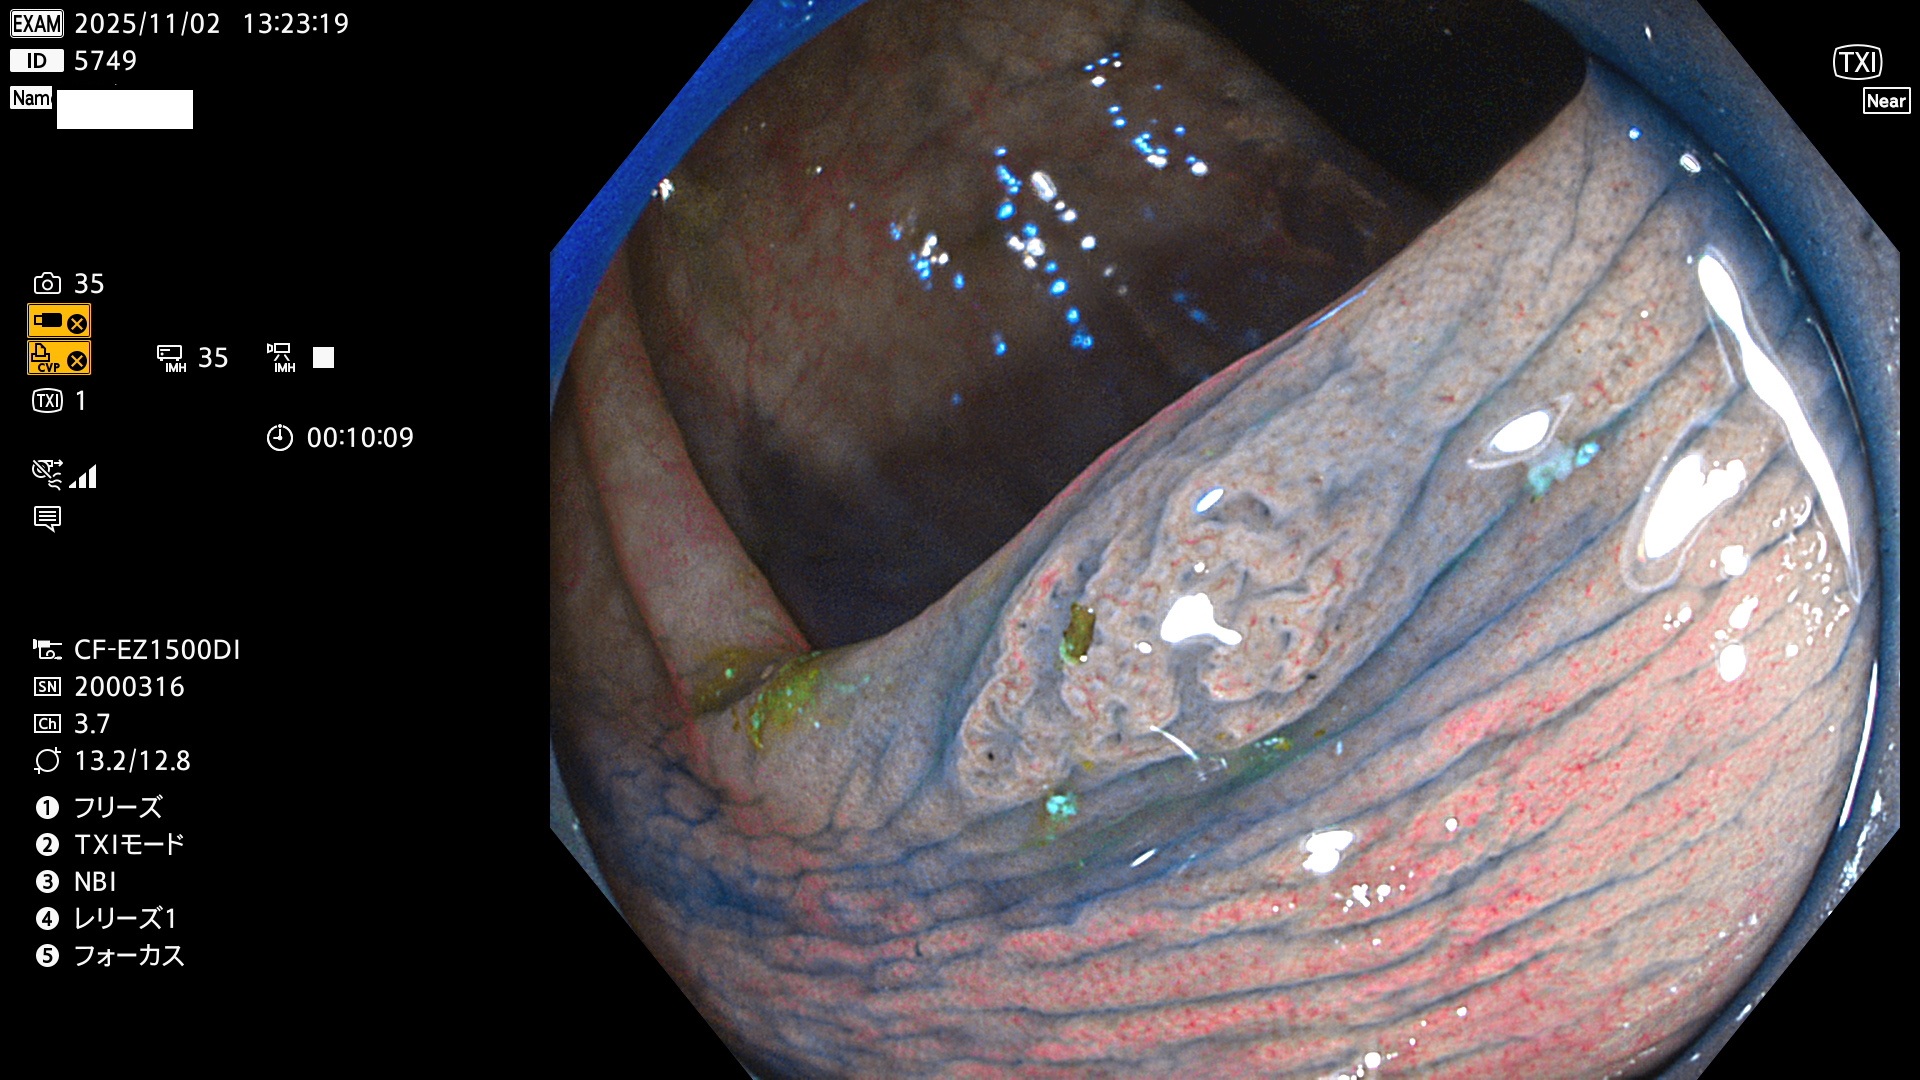

完全に平坦な物をUb、陥凹している物をUcと呼びます。Ubは認識が困難で、Ucはびらん(炎症)と紛らわしいために見落とされやすく、「内視鏡後・大腸癌」の原因になります。

専門的)Uc=De Novo癌? 内視鏡の解像度が低かった時代、このような説もありました。しかし今日の高精度内視鏡では良性の微小なUc型腺腫(APC遺伝子異常の腺腫)が日常的に見つかります。Ucこそが多段階発癌(Adenoma-Carcinoma Sequence)のMain Routeです。

毎週の検査(木・金・土・日)に発見されたUbとUc型・腺腫を、その週の日曜の夜にUPし1週間、提示します。

2025年10月30日〜11月2日の4日間(40件)9個 (Uc_ADR=9個/40人=23%)